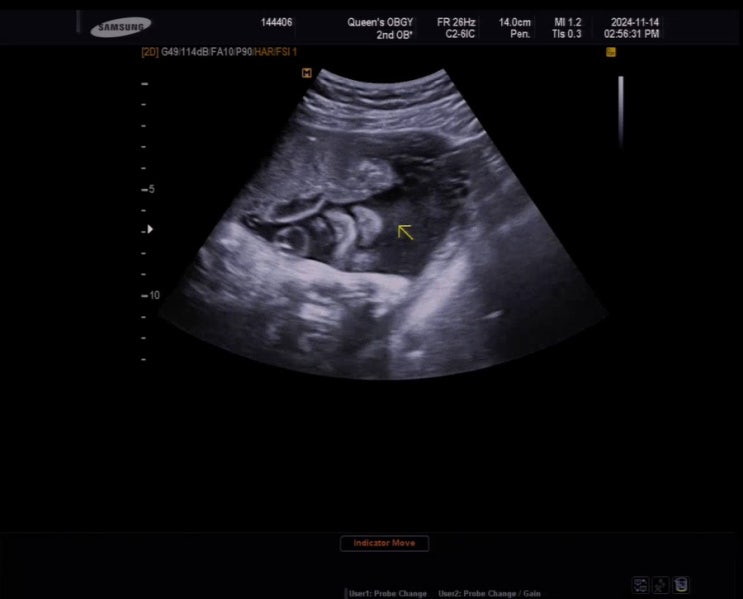

[임신기록] 긴가민가 가진통 & 내진 _38주

37주차 진료가 마지막이길 바랬지만 시간은 빠르게 흘러 일주일이 번개처럼 지났고요 저는 38주가 되었습니...

[임신기록] 맥수술 실밥제거하고 자연진통 기다리기 _36&37주

이 포스팅이 마지막 임신기록일지도 모르니까 상세하게(?) 읊어볼게요 [36주] 이제는 증말루 심각하게 맞는...